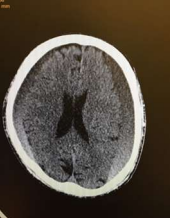

Radiology

Fig 1,2,3,4,5,6,7,8,9,10,11,12,13,14,15

Thirty eight out of Eighty-two patients were treated conservatively and were studied (25 men; 13 females, mean age, 64.8 years). The average thickness of the hematoma was 18 mm, the mean midline shift was 4.7 mm, and the average attenuation value of bleed on computed tomography scan was 33.5. Thirty-eight were treated successfully with steroid treatment, whereas 44 patients required surgery. The female gender, less midline shift, less density (Hounsfield units) was noted to be associated with successful medical treatment. We propose a grading based on the total score given to the midline shift and density.